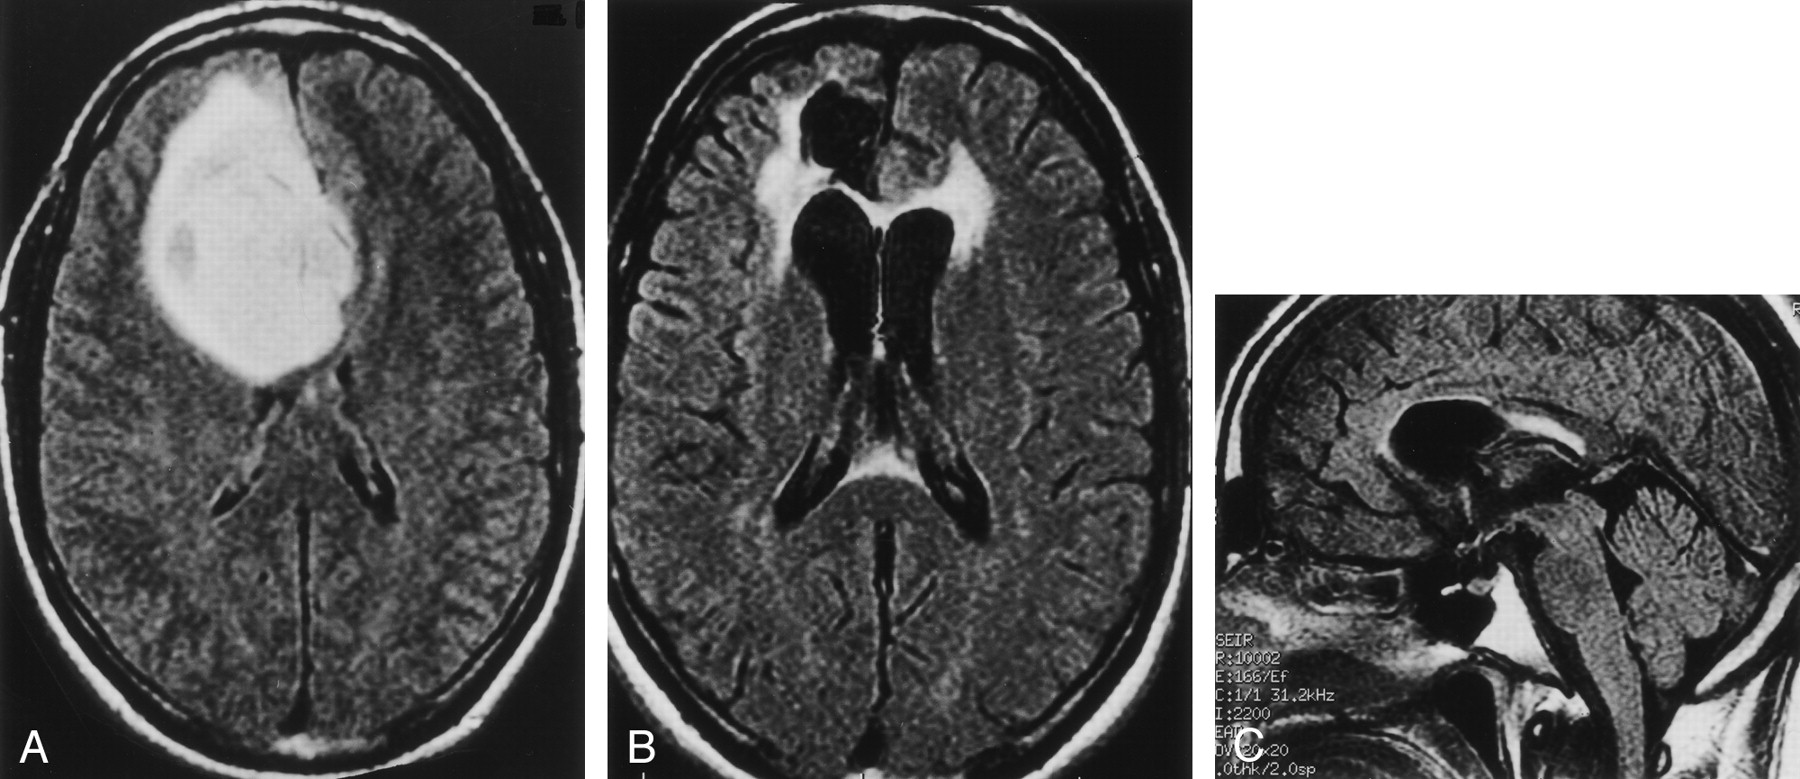

Case of a 32-year-old man (patient 12 in Table) with geminocystic astrocytoma.

A, Axial FLAIR MR image (10,002/166/1) obtained 0.8 months before radiation therapy shows normal signal intensity in the splenium.

B, Axial and C, sagittal FLAIR images (10,002/166/1) obtained 5.8 months after radiation therapy demonstrate a bright focus of abnormal signal intensity in the anterior subependymal region of the splenium of the corpus callosum (grade 2).